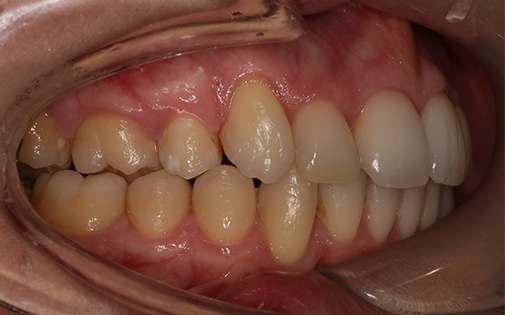

This patient presented with a very severe malocclusion (i.e. irregularity of her teeth and jaws). The ideal treatment recommended was removal of four teeth, upper and lower fixed braces and surgery to her jaws. However, the patient was not keen on the idea of surgery so she offered the alternative of removal of two upper teeth and Invisalign clear aligners. With the expertise of our specialist orthodontists, even the most challenging cases can be treated successfully with Invisalign.